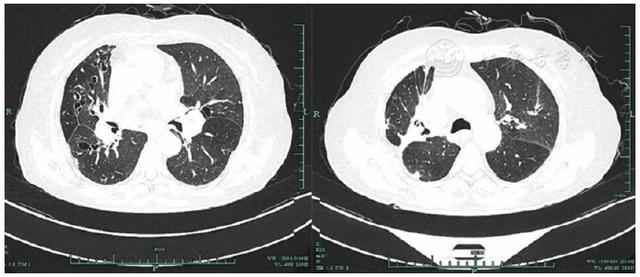

共317例TOPD患者完成影像學檢查。TOPD患者肺部CT顯示多處鈣化結(jié)節(jié)等結(jié)核瘢痕,部分患者存在一定程度的肺氣腫和支氣管擴張征象,見圖1,圖2,圖3。TOPD患者左肺上、舌、下葉的結(jié)核瘢痕陽性分別為176例(55.5%)、120例(37.9%)和126例(39.7%),右肺上、中、下葉的結(jié)核瘢痕陽性分別為215例(67.8%)、142例(44.8%)、168例(52.9%);左肺的支氣管擴張征象主要集中在左肺舌葉,右肺主要位于中葉、下葉;肺氣腫在雙肺間分布較為均衡,見圖4。

Figure 2

Figure 2 Pulmonary imaging findings of TOPD patients